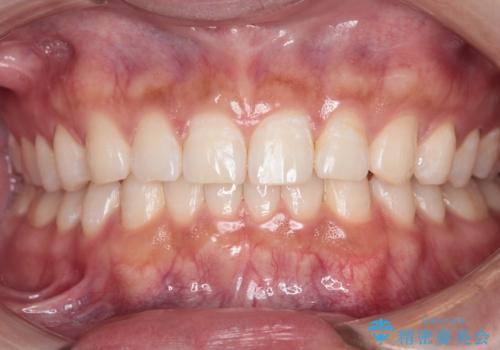

【インビザライン】正中離開を治したい

再矯正ということでがたつきはなくきれいに並んでいましたが、上下のアーチ(歯列弓)の大きさのバランスが悪く、結果的に後戻りの原因になってしまっていました。今回は下のアーチを小さくするためにIPRを行い、かみ合わせのバランスを治しながら前歯の隙間を閉じました。